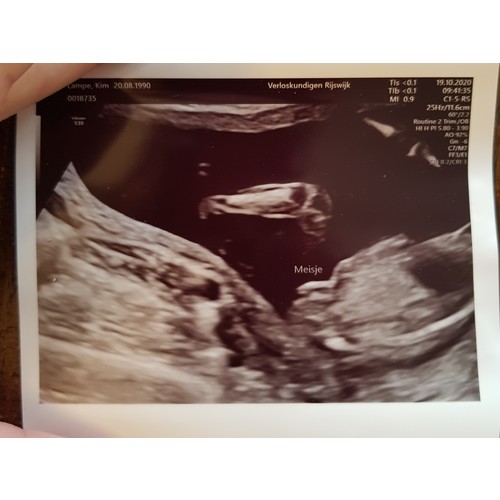

Bij mij ging ze ook meteen voor het zij aanzicht. De echoscopiste zei meteen dan kan ik het het beste meteen zien. Is een meisje. Mijnes is wel gedaan vandaag op 16+2 Dus is zeker geen nub meer. Ze zei dat dat witte staafje een schaambeen/bot is en dat bij jongetjes daarboven heel duidelijk een piemeltje met balletjes had gezeten. Daarna nog wat shots van onder gezien en ook daar was echt 0,0 te zien aan een uitsteeksel 🤣 maar zij pakte dus ook niet een pottyshot om het te zien...

Dat ding wat erboven zweeft is trouwens een gebogen beentje🤣